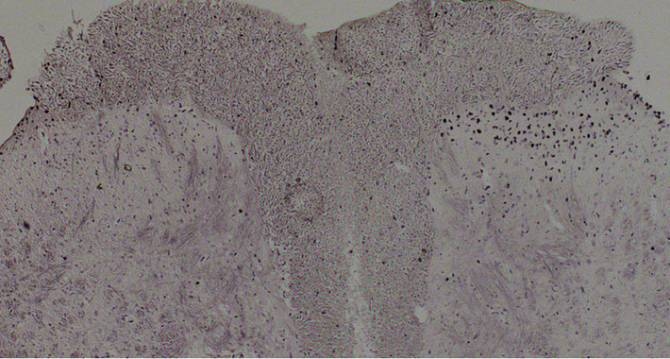

Imagen al microscopio de un corte de médula espinal. En él pueden verse las células que están activadas (en negro en la mitad derecha de la imagen). (Foto: Cortesía de Jose Vicente Torres)

Técnicamente, el equipo en el que trabaja el experto español ha demostrado en ratones que una población de neuronas superficiales de la médula espinal controla un marcador epigenético conocido como pS10H3.

“Hemos observado este efecto después de utilizar diferentes modelos animales de dolor: inducción de quemaduras, aplicación de capsaicina o estimulación eléctrica del nervio”, apunta Torres Pérez.